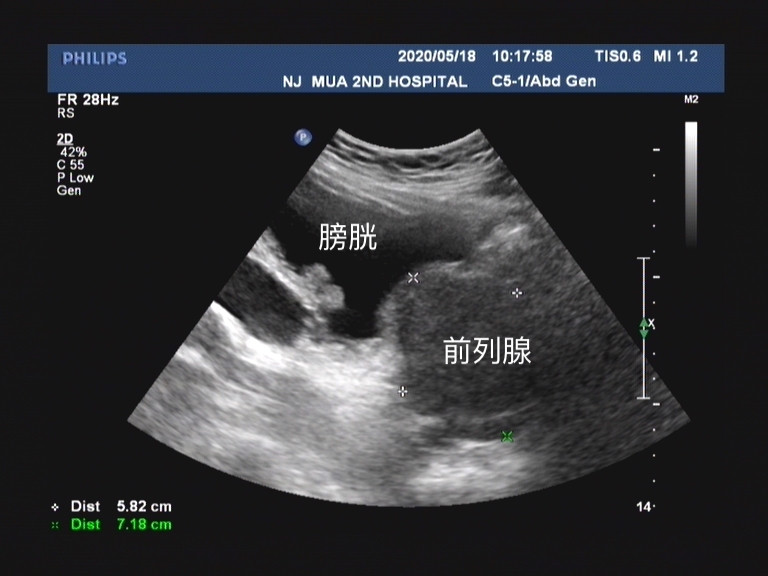

前列腺疾病和泌尿系感染

伴有前列腺疾病的老年患者在发生急性脑卒中时, 因受到突发的刺激,容易发生急性尿潴留 。老年人的输尿管、膀胱容易形成憩室导致细菌存留, 易发生泌尿系感染 ,可加重尿*禁失**的发生。